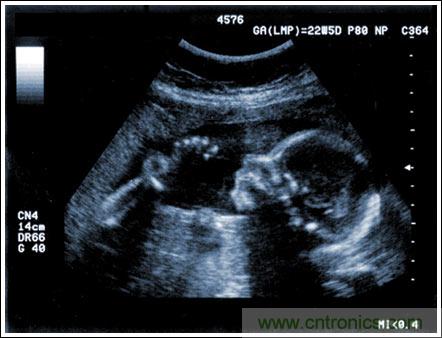

通過發(fā)射超聲能量進(jìn)入人體,接收并處理返回的反射信號(hào),相控陣超聲系統(tǒng)可以生成體內(nèi)器官和結(jié)構(gòu)的圖像,映射血液流動(dòng)和組織運(yùn)動(dòng),同時(shí)提供高準(zhǔn)確度的血流速度信息。傳統(tǒng)設(shè)計(jì)中,構(gòu)建這樣的成像系統(tǒng)需要大量的高性能相控陣發(fā)射器和接收器,使得車載設(shè)備體積龐大且價(jià)格昂貴。近年來,隨著集成工藝的進(jìn)步,設(shè)計(jì)人員能夠獲得小尺寸、低成本而且高度便攜的成像系統(tǒng)方案,并可達(dá)到接近大型成像設(shè)備的性能指標(biāo)。而新的設(shè)計(jì)挑戰(zhàn)依然存在,即在進(jìn)一步提高方案集成度的同時(shí)提高系統(tǒng)性能和診斷能力。